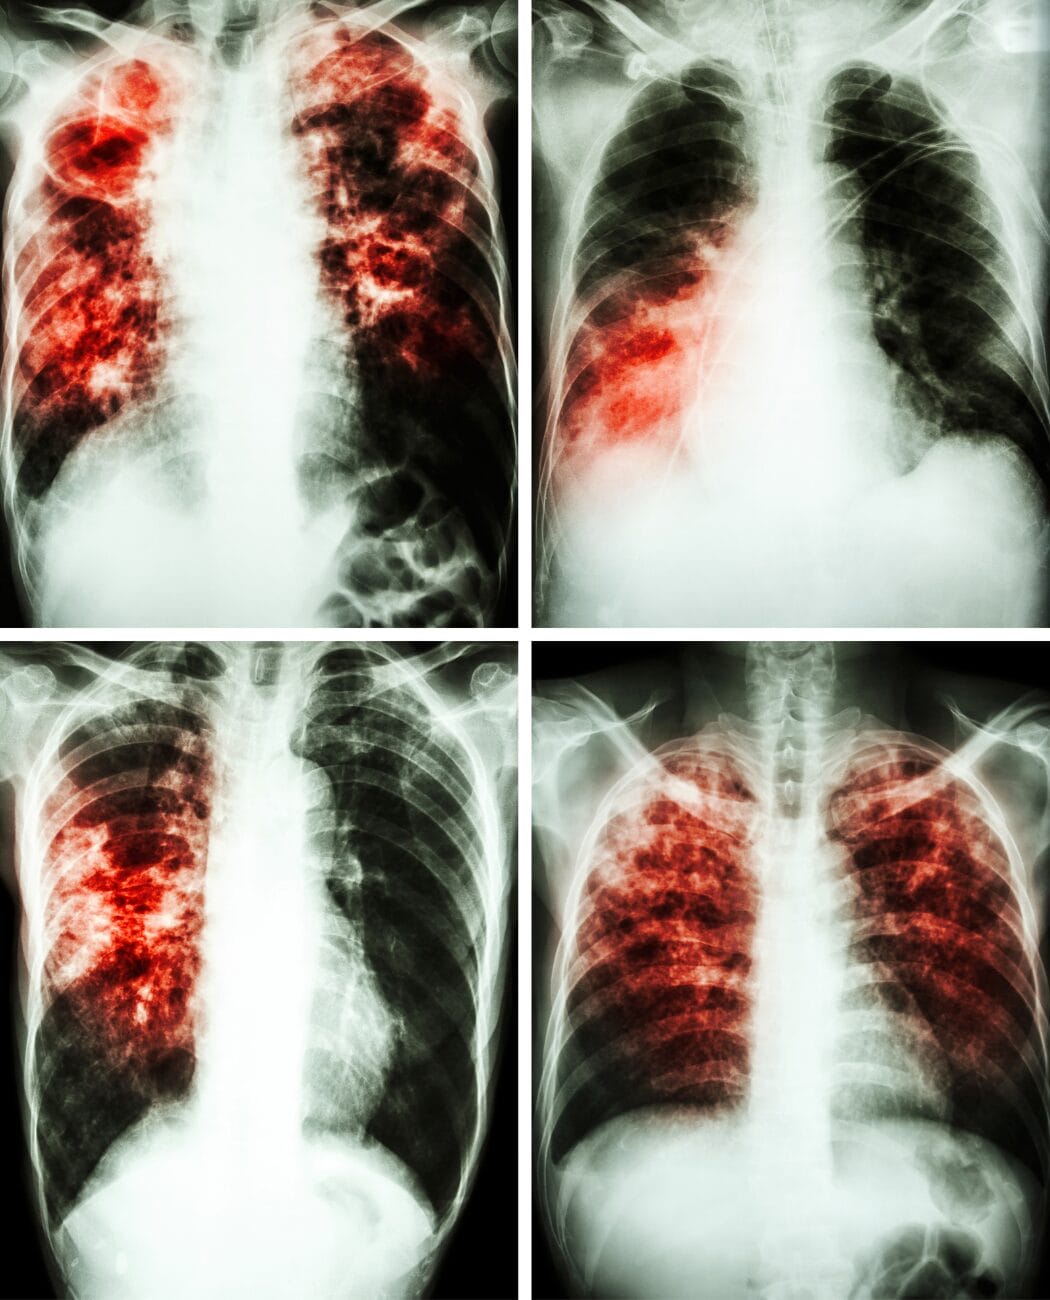

Diagnosing lung and breathing disorders involves a comprehensive assessment of an individual's respiratory health to identify any abnormalities or impairments. This process often includes a combination of:

Once a precise diagnosis is established, healthcare professionals can formulate tailored treatment plans to address the specific disorder or condition. There are a number disorders or conditions that RRTs handle on a daily basis. They can include:

Treatment methods may vary depending on the nature and severity of the respiratory issue, ranging from lifestyle modifications and medication regimens to more advanced interventions such as respiratory therapies or surgical procedures. The ultimate goal is to optimize lung function, alleviate symptoms, and enhance overall respiratory well-being, ensuring that individuals receive personalized and effective care based on their unique medical needs.